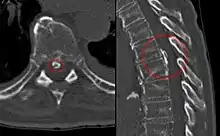

Imaging

Magnetic resonance imaging (MRI) is the preferred modality for the evaluation of back pain and visualization of bone, soft tissue, nerves and ligaments. X-rays are a less costly initial option offered to patients with a low clinical suspicion of infection or malignancy, and they are combined with laboratory studies for interpretation.

Imaging is not warranted for most patients with acute back pain. Without signs and symptoms indicating a serious underlying condition, imaging does not improve clinical outcomes in these patients. Four to six weeks of treatment is appropriate before consideration of imaging studies. If a serious condition is suspected, MRI is usually most appropriate. Computed tomography is an alternative if MRI is contraindicated or unavailable.[37] In cases of acute back pain, MRI is recommended for those with major risk factors or clinical suspicion of cancer, spinal infection or severe progressive neurological deficits.[38] For patients with subacute to chronic back pain, MRI is recommended if minor risk factors exist for cancer, ankylosing spondylitis or vertebral compression fracture, or if significant trauma or symptomatic spinal stenosis is present.[38]